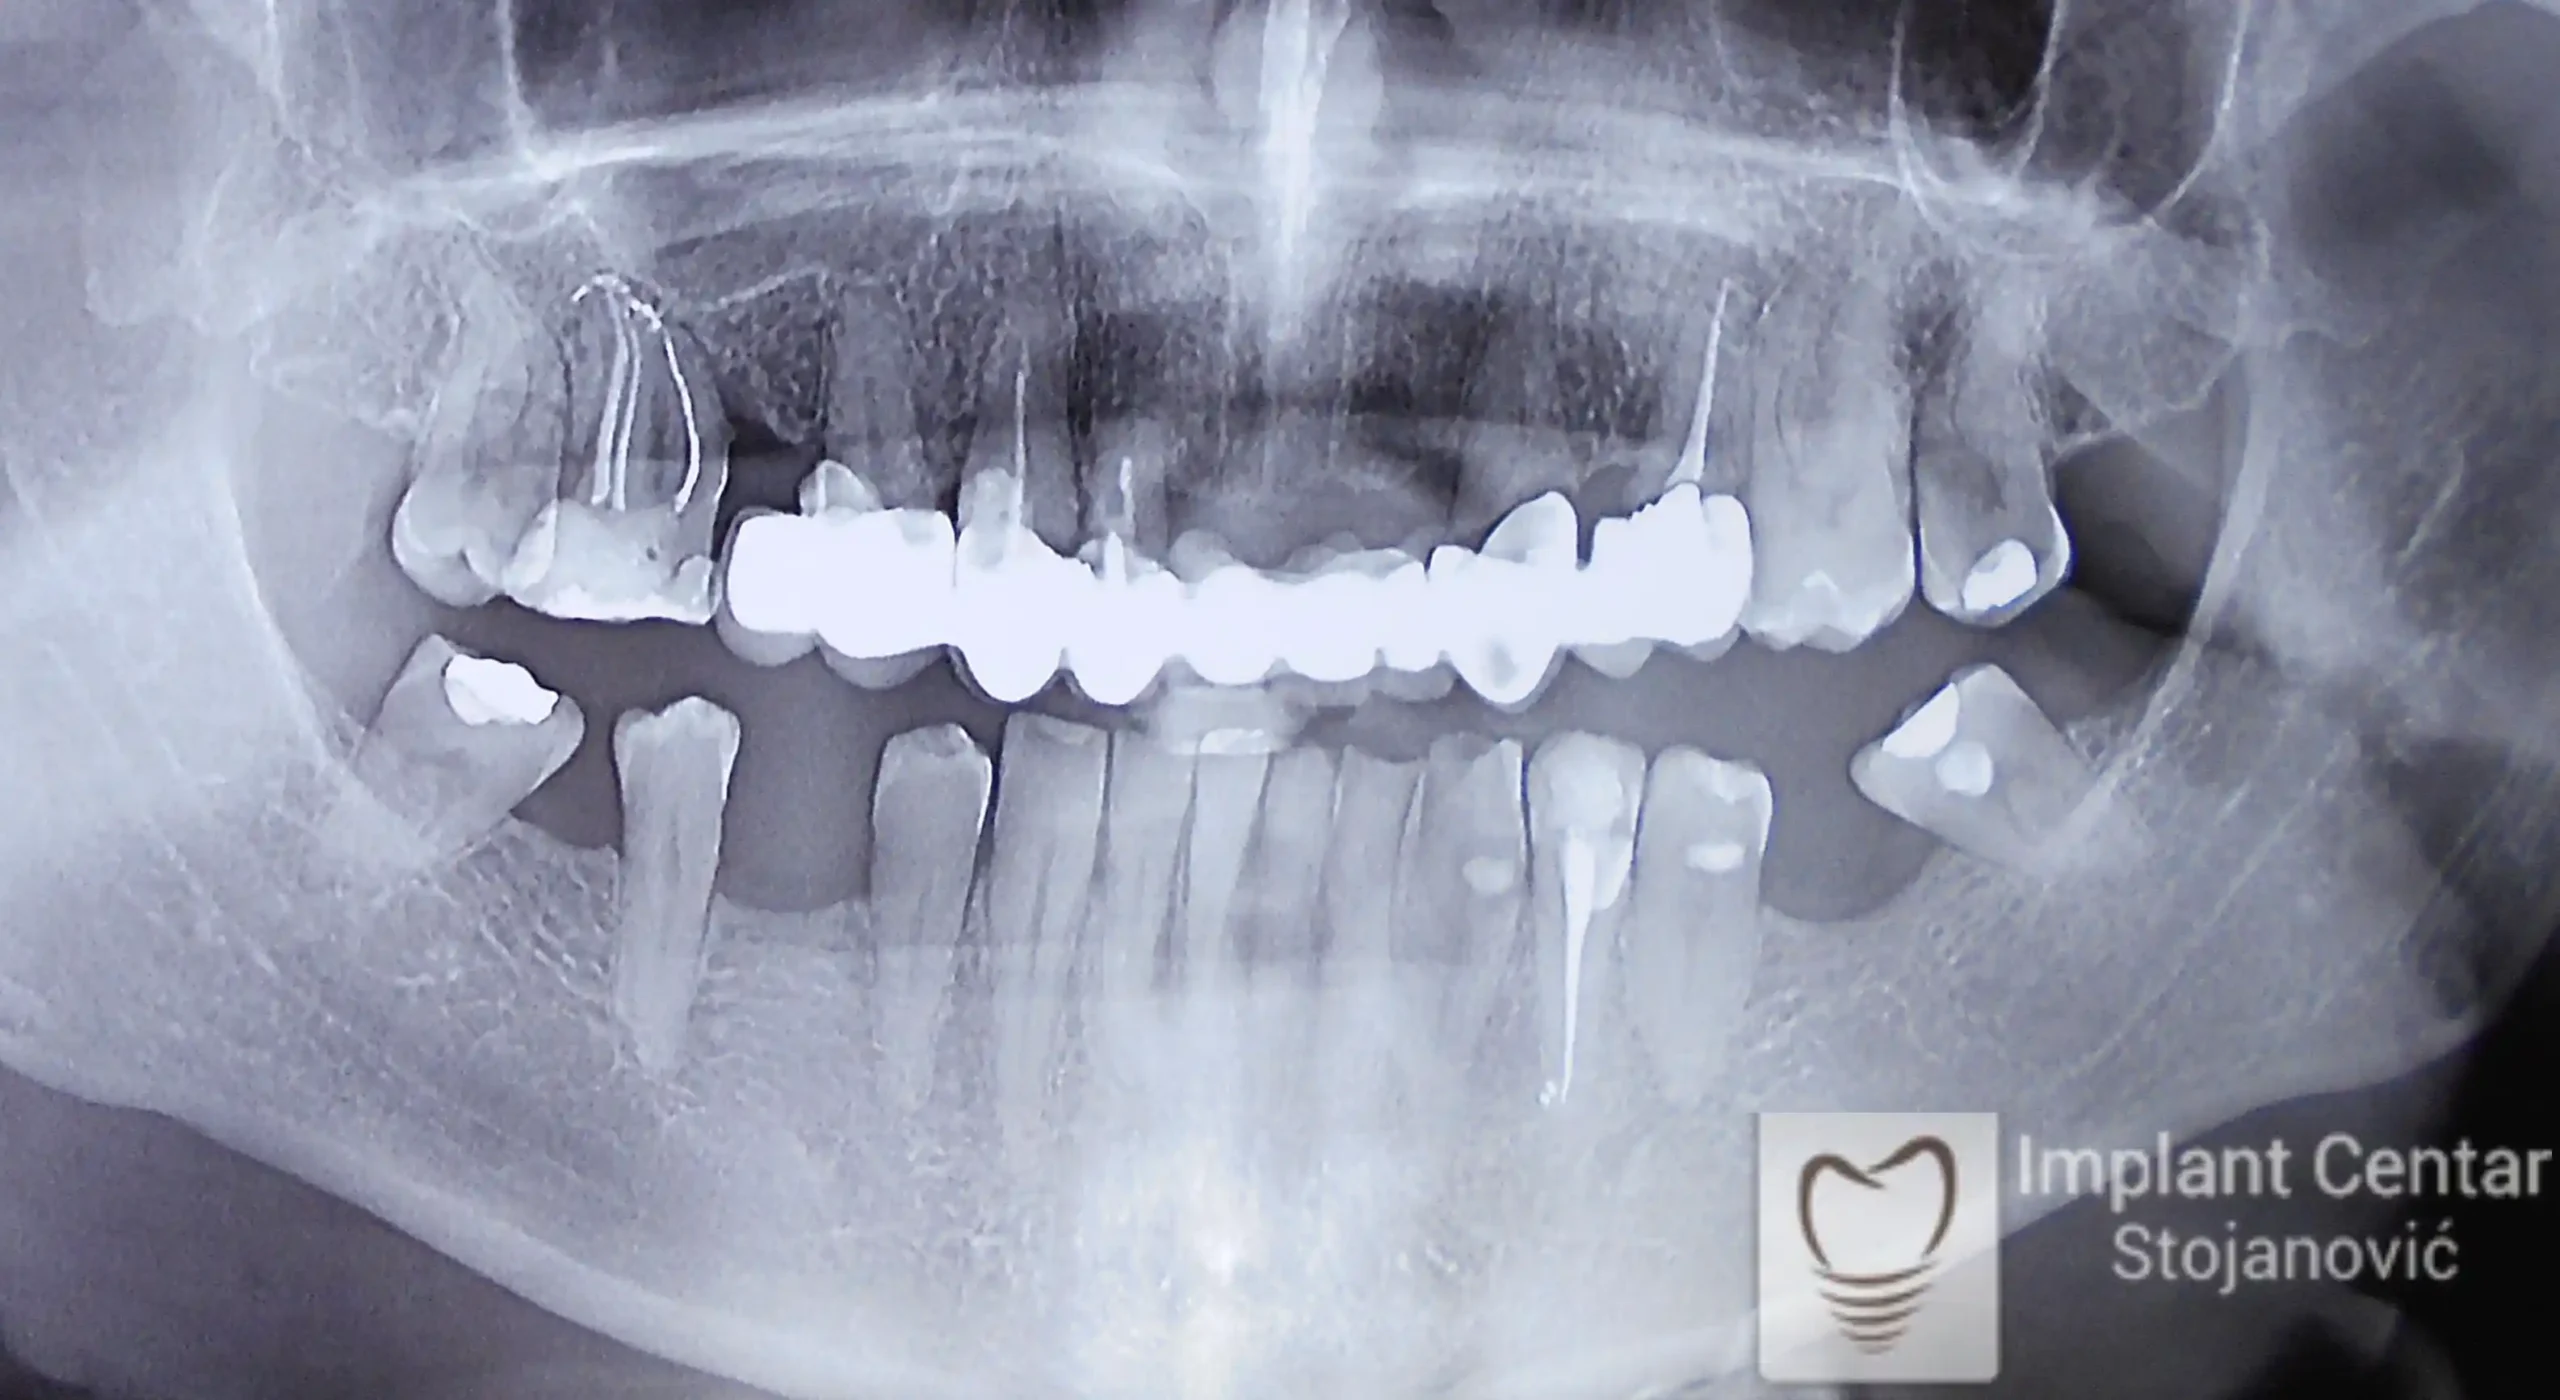

Pacijent je došao sa starim, dotrajalim mostovima koji nisu pružali adekvatnu funkciju niti estetiku, a u bočnim regijama gornje i donje vilice prisutna je bila mala količina kosti. Nakon detaljnog pregleda i analize snimaka, doneta je odluka o skidanje starih mostova i vađenju preostalih zuba loše biološke vrednosti.

Ugrađen je optimalan broj implantata, čime je obezbeđena pravilna raspodela sila žvakanj na vilične kosti i dugotrajnost protetskog rada. Pacijent je definitivno zbrinut fiksnim cirkonijum-keramičkim mostovima na implantatima, koji su omogućili vraćanje pravilne funkcije žvakanja, postizanje maksimalne estetike i povratak samopouzdanja, vraćajući osmeh na lice.